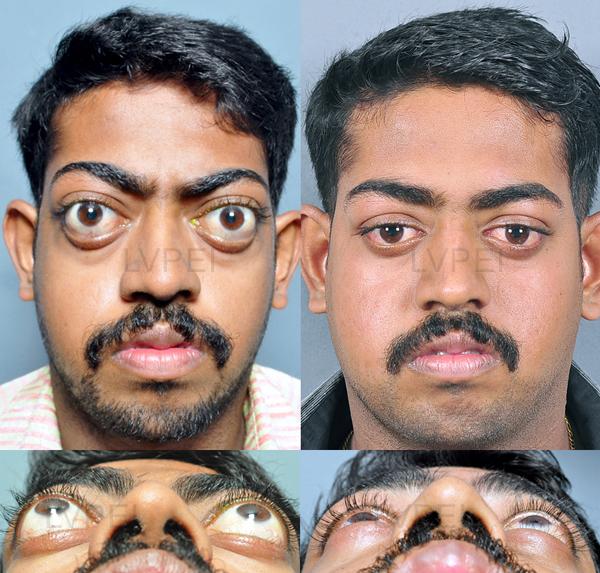

- Reputation

6. Orbital decompression

6. Orbital decompression

13. Orbital box osteotomy